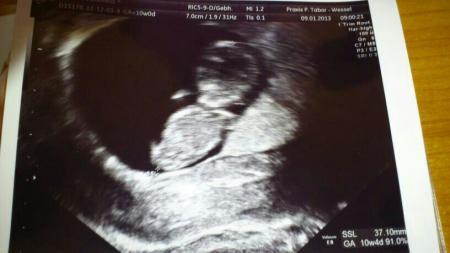

Es ist nur merkwürdig, am Anfang musste ich ständig auf die Toilette, hatte Brustschmerzen... Jetzt lässt es langsam nach, aber wahrscheinlich mach ich mir einfach zu viele Gedanken :-)... War ja erst Mittwoch beim FA, da war alles super... Siehe das Bild :-)

Bild zu